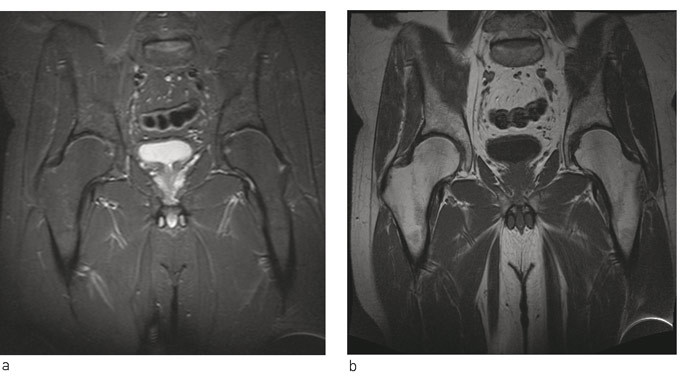

På bakgrunn av flere kasuistikker hvor man beskrev mulig effekt av peroral bisfosfonatbehandling ved benmargsødemsyndrom, startet vi med alendronat 70 mg en gang i uken (9). Pasienten ble fulgt opp med regelmessige telefonkonsultasjoner, og både smerter og funksjonsnivå bedret seg gradvis. Ved kontroll seks måneder etter symptomdebut var han smertefri og kunne belaste benet fullt. Ny MR-undersøkelse viste full tilbakegang av benmargsødemet i caput femoris, men noe ødem i acetabulum. Etter ytterligere tre måneder var MR bekken og hofteledd helt normalisert (fig 2). Bentetthetsmåling viste da T-skår –2,6, og –2,1 i henholdsvis høyre og venstre hofte. Videre oppfølging av endokrinolog viste vedvarende lett forhøyet PTH-nivå uten at det ble funnet noen sikker årsak til dette.

På MR-bilder er benmargsødem karakterisert av diffust utbredte forandringer i form av væskelignende signal fra benmarg med nedsatt signalintensitet på T1-vektede bilder og økt signalintensitet på væskesensitive sekvenser, f.eks. T2-vektede bilder med fettsuppresjon eller «short tau inversion recovery»-sekvens (STIR) (1).